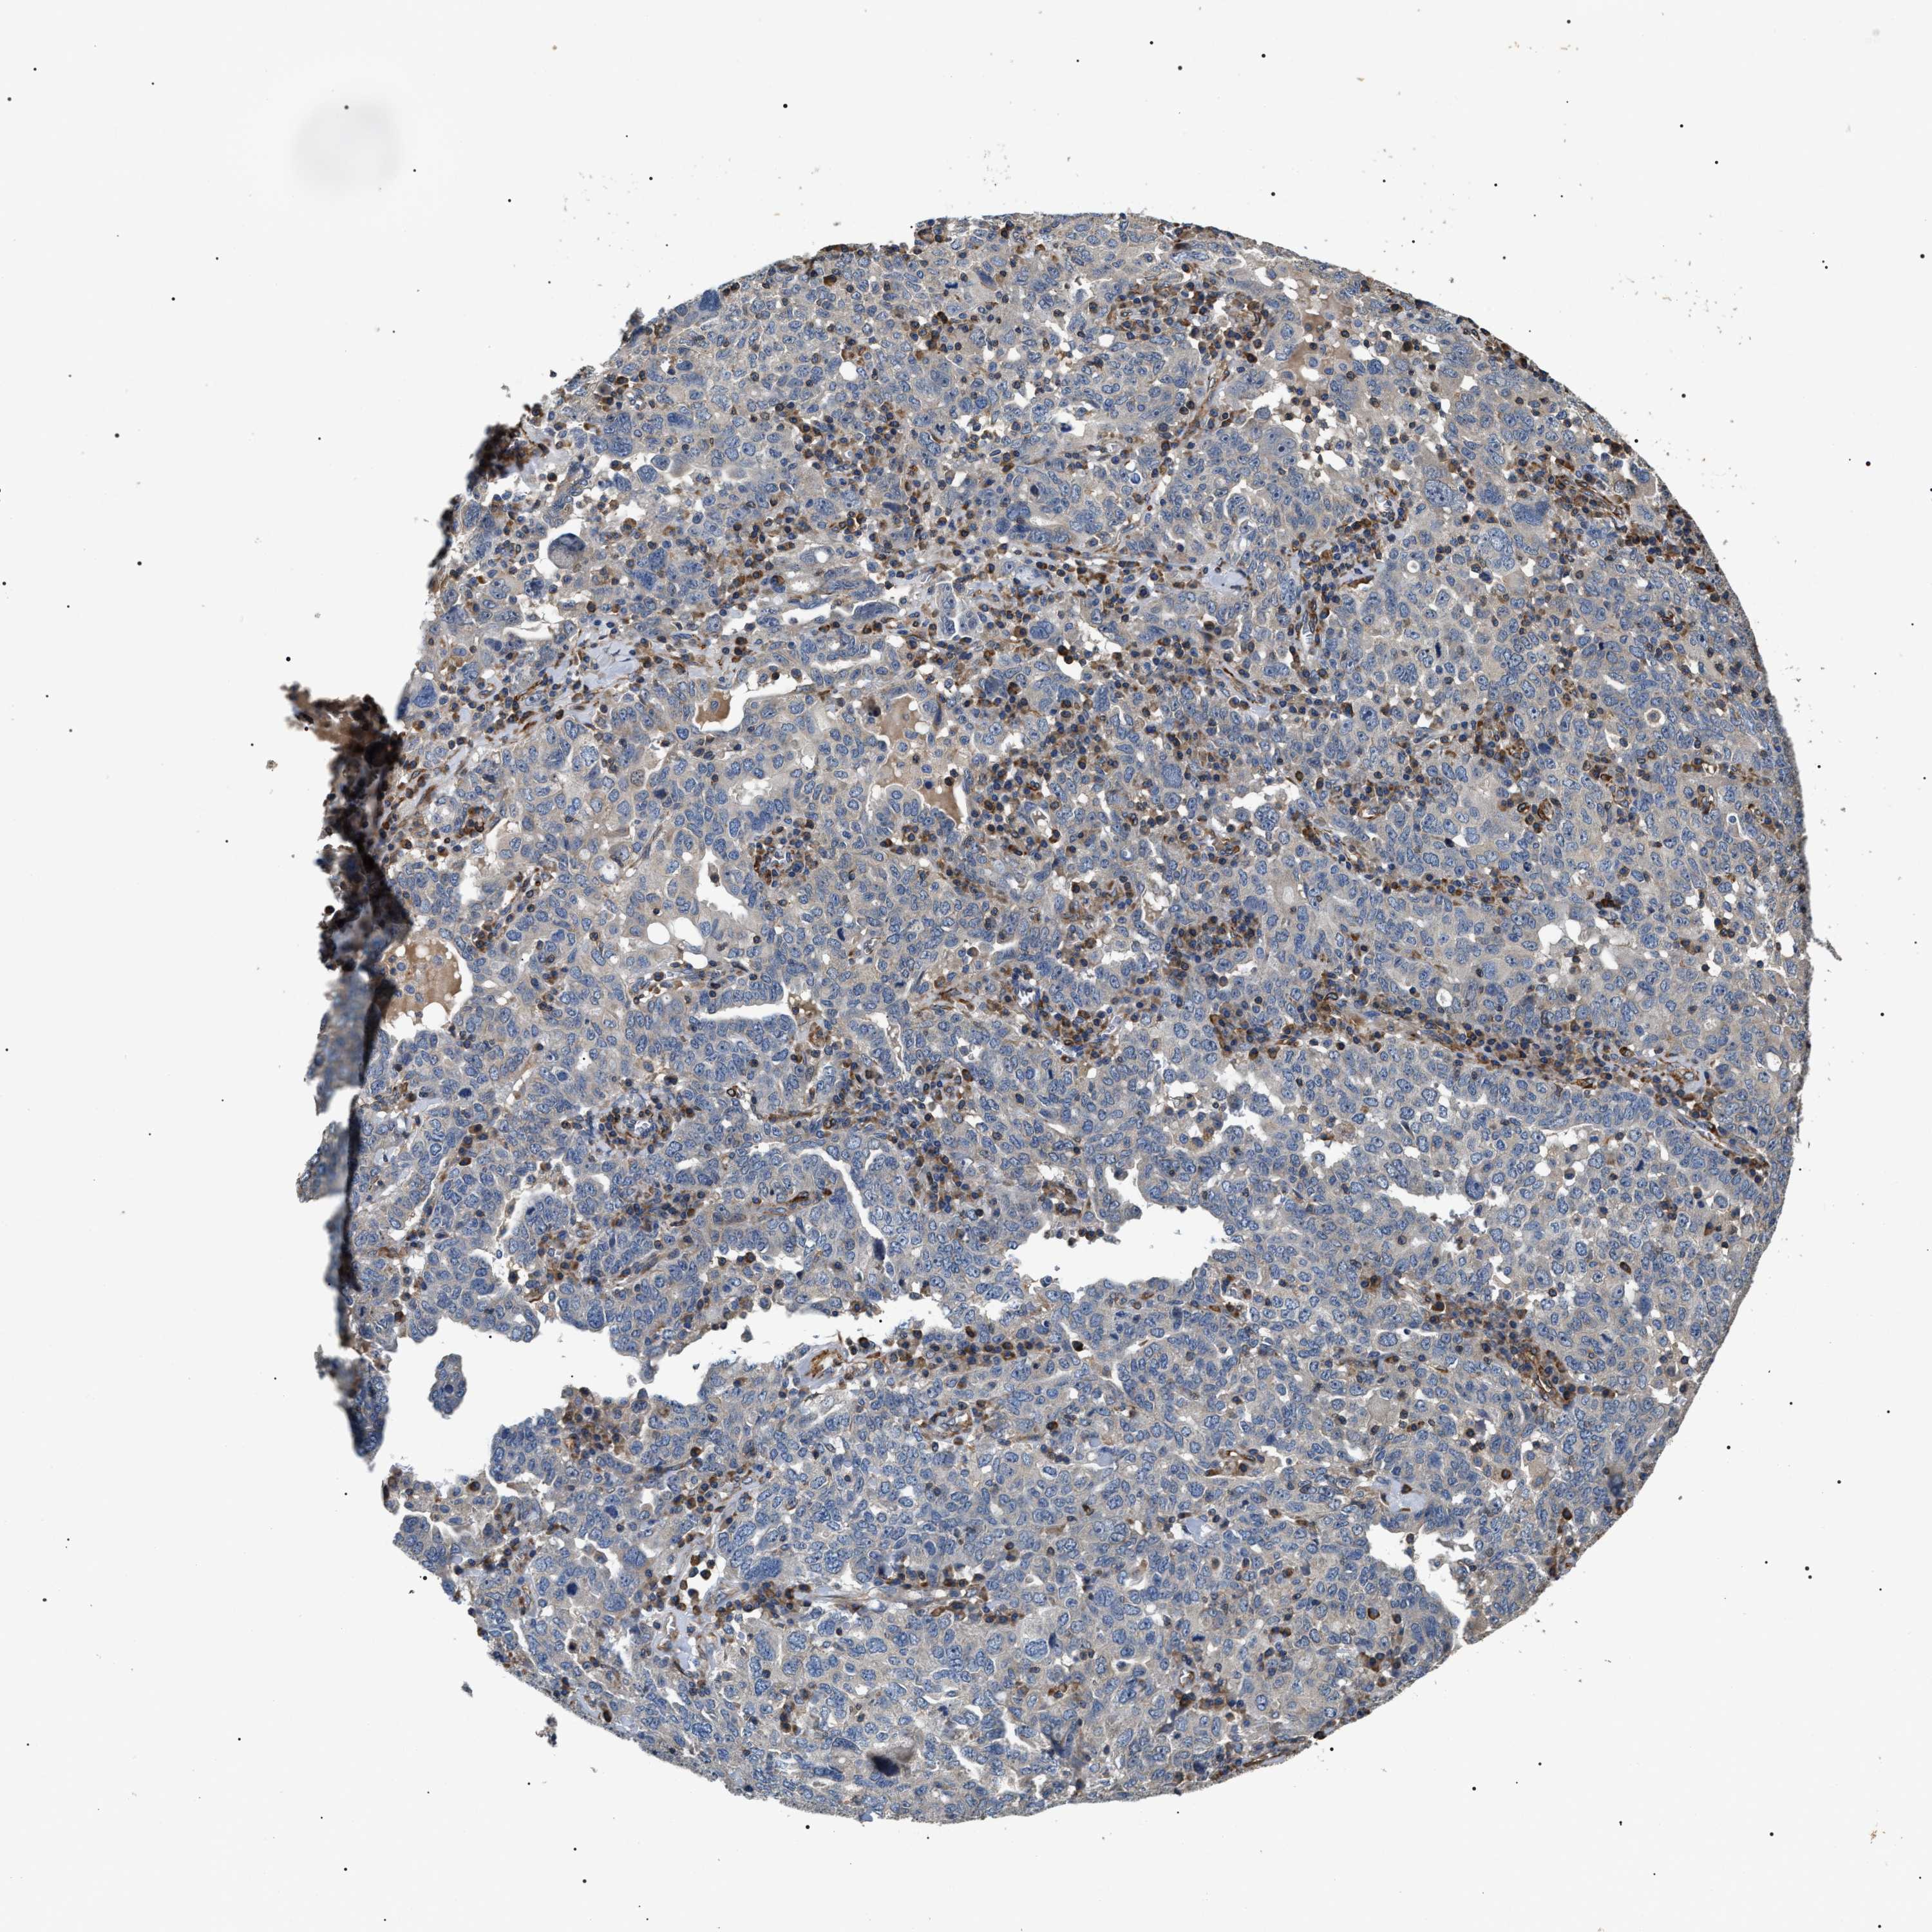

OVARIAN CANCER - Protein expressioni

A mouse-over function shows sample information and annotation data. Click on an image to view it in a full screen mode. Samples can be filtered based on level of antibody staining by selecting one or several of the following categories: high, medium, low and not detected. The assay and annotation is described here.

Note that samples used for immunohistochemistry by the Human Protein Atlas do not correspond to samples in the TCGA dataset.

Antibody stainingi

Antibody staining in the annotated cell types in the current human tissue is reported as not detected, low, medium, or high, based on conventional immunohistochemistry profiling in selected tissues. This score is based on the combination of the staining intensity and fraction of stained cells.

Each image is clickable and will lead to virtual microscopy that enables deeper exploration of all samples and also displays staining intensity scores, fraction scores and subcellular localization as well as patient and tissue information for each sample.

Antibody HPA020386

Staining

High

Medium

Low

Not detected

Intensity

Strong

Moderate

Weak

Negative

Quantity

>75%

75%-25%

<25%

None

Location

Nuclear

Cytoplasmic/membranous

Cytoplasmic/membranous,nuclear

Cystadenocarcinoma, serous, NOS

Carcinoma, endometroid

Cystadenocarcinoma, mucinous, NOS

Carcinoma, NOS